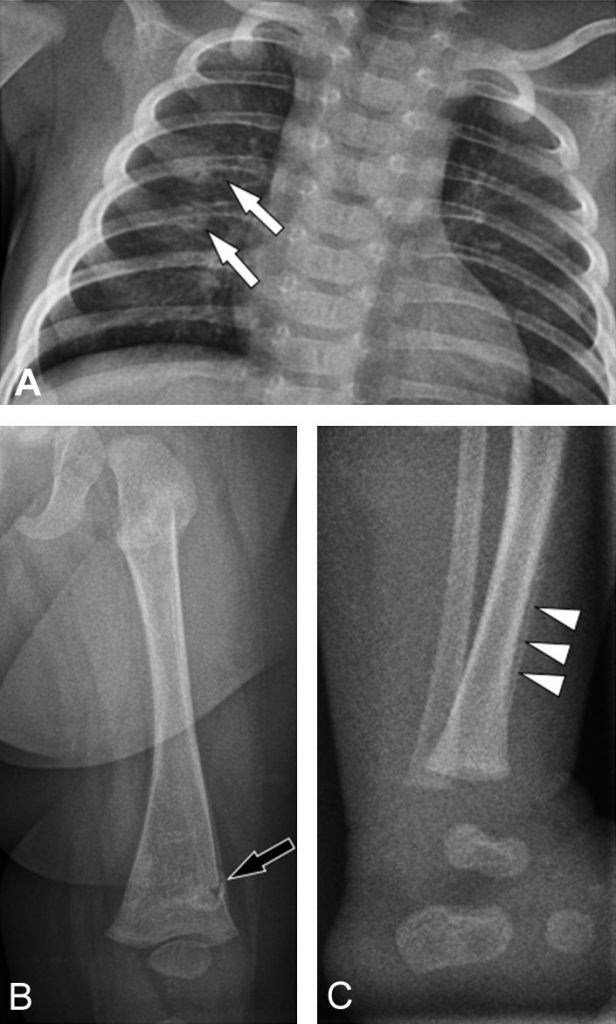

Fig. 117.2 Fractures d’âges différents.

Fractures semi-récentes des arcs postérieurs des 5e à 6e côtes gauches avec cal osseux en formation (flèches blanches) (A). Fracture métaphysaire fémorale distale inhabituelle récente chez le même enfant (flèche noire) (B). Exemple d’hématome sous-périosté chez un autre nourrisson (têtes de flèche) (C).

Elles doivent être d’excellente qualité et effectuées segment par segment, à la recherche de fractures, souvent multiples et parfois d’âges différents (syndrome de Silverman), de siège particulier (arc postérieur des côtes, sternum, omoplate, etc.) ou inhabituel pour l’âge de l’enfant (épiphysométaphysaire) (figure 117.2).